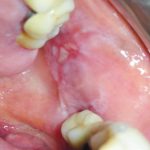

Fig. 6A Caso clinico di lesioni da pemfigoide indotto da farmaci caratterizzate da aeree bollose ed erosive diffuse su mucose geniene e gengive.